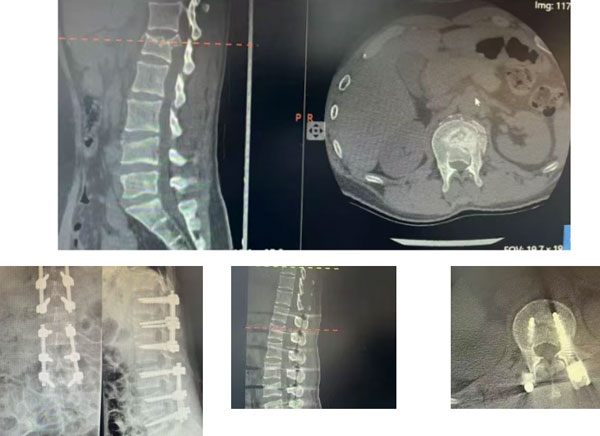

患者孙女士(化名)意外发生车祸导致腰背部剧烈疼痛,双下肢瞬间阵发性麻木、疼痛,活动受限,被紧急送入我院急诊后,影像学检查结果令人揪心:L1、L4椎体爆裂性骨折,多发肋骨骨折。

“椎体像被压碎的鸡蛋壳,碎骨片严重突入椎管,把脊髓和马尾神经压得死死的。”骨科副主任王自鸿主任医师回忆,“这是骨科最危急的重症之一,若不及时干预,患者将面临永久性瘫痪的风险。”

重建稳定:麻醉成功后,小心摆放体位,避免二次损伤,经肌间隙入路微创显露,精准置入椎弓根螺钉,安装连接杆,恢复脊柱生理曲度及脊柱稳定性,为患者后期下地行走奠定力学基础。

间接减压:在安装连接杆并适度撑开,固定后,术中透视见压缩及突入椎管的骨折块基本复位,避免了开放椎管直接减压,减少了出血及对脊柱稳定结构的进一步损伤,术中出血不足100ml。

历经2个多小时的鏖战,手术顺利完成。术后复查显示,椎管内压迫完全解除,神经“松绑”成功。